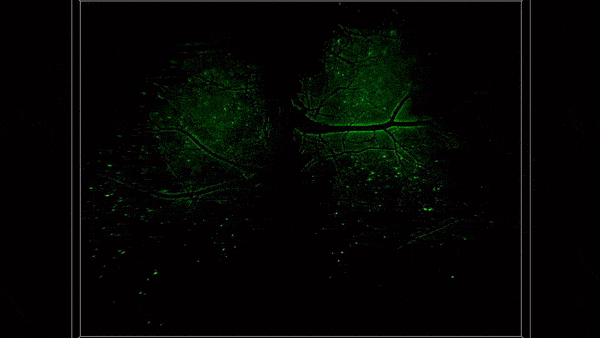

小鼠全脑皮层范围三维神经成像

目前,研究团队利用RUSH3D系统在脑科学、免疫学、医学与药学等多学科产出一系列成果。例如,首次在活体小鼠上以单细胞分辨率实现了覆盖大脑皮层2/3层的高速长时程三维观测,捕捉了多感官刺激下皮层各脑区的各异性响应模式,能够连续多天以单神经元精度追踪大规模神经响应;首次观测到急性脑损伤后多脑区的免疫反应,发现大量中性粒细胞从非血管区域往脑内的迁移与回流过程;首次在小鼠免疫反应过程中同时观测到了淋巴结内多个生发中心的形成过程,以及T细胞在不同生发中心之间的迁移现象。

急性脑损伤后全皮层范围单细胞水平免疫反应